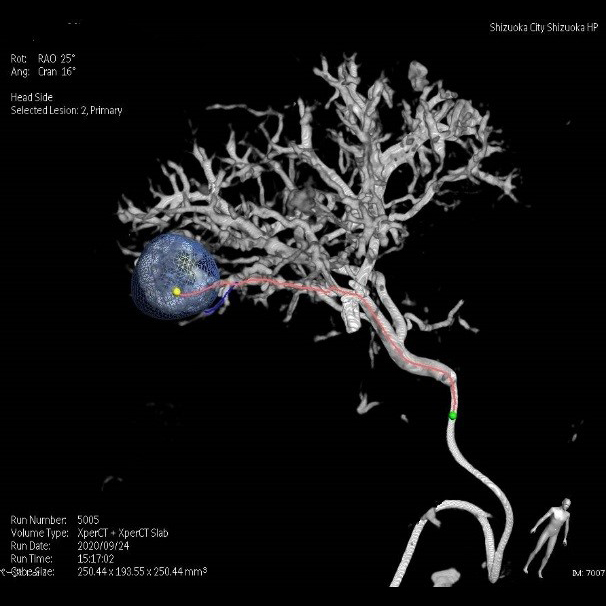

脳血管撮影

脳血管撮影では、頭頸部の血管をカテーテルから造影剤を流して撮影します。血管の走行を観察したり、必要に応じて血管の狭窄や閉塞を広げる治療や、動脈瘤をコイルで塞栓する治療、脳腫瘍などへの栄養血管に対して手術前の塞栓術を行ったりします。脳の血管をみる検査にはCTやMRIなどといった撮影もありますが、血管撮影装置での脳血管撮影ではそれらよりも細かい血管の状態まで観察することができます。

術前流速検査

術中MPR

術後3D

脳血管の還流画像

内頚動脈狭窄症へのステント術

CT、MRIの画像と血管撮影での

造影画像を重ね合わせた3D画像(脳腫瘍)